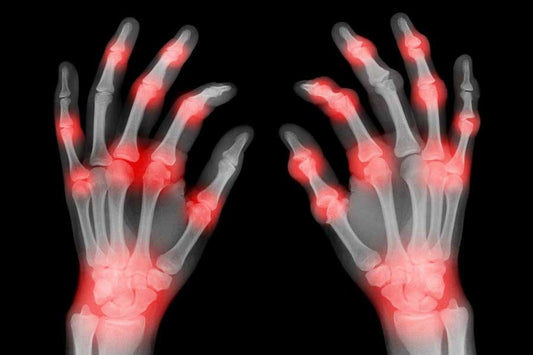

Omega-3s to relieve arthritis pain

If you or someone you know suffers from Arthritis, a debilitating, painful disease, you know how much it can reduce quality of life. Painful, swollen and inflamed joints are the hallmark symptoms...